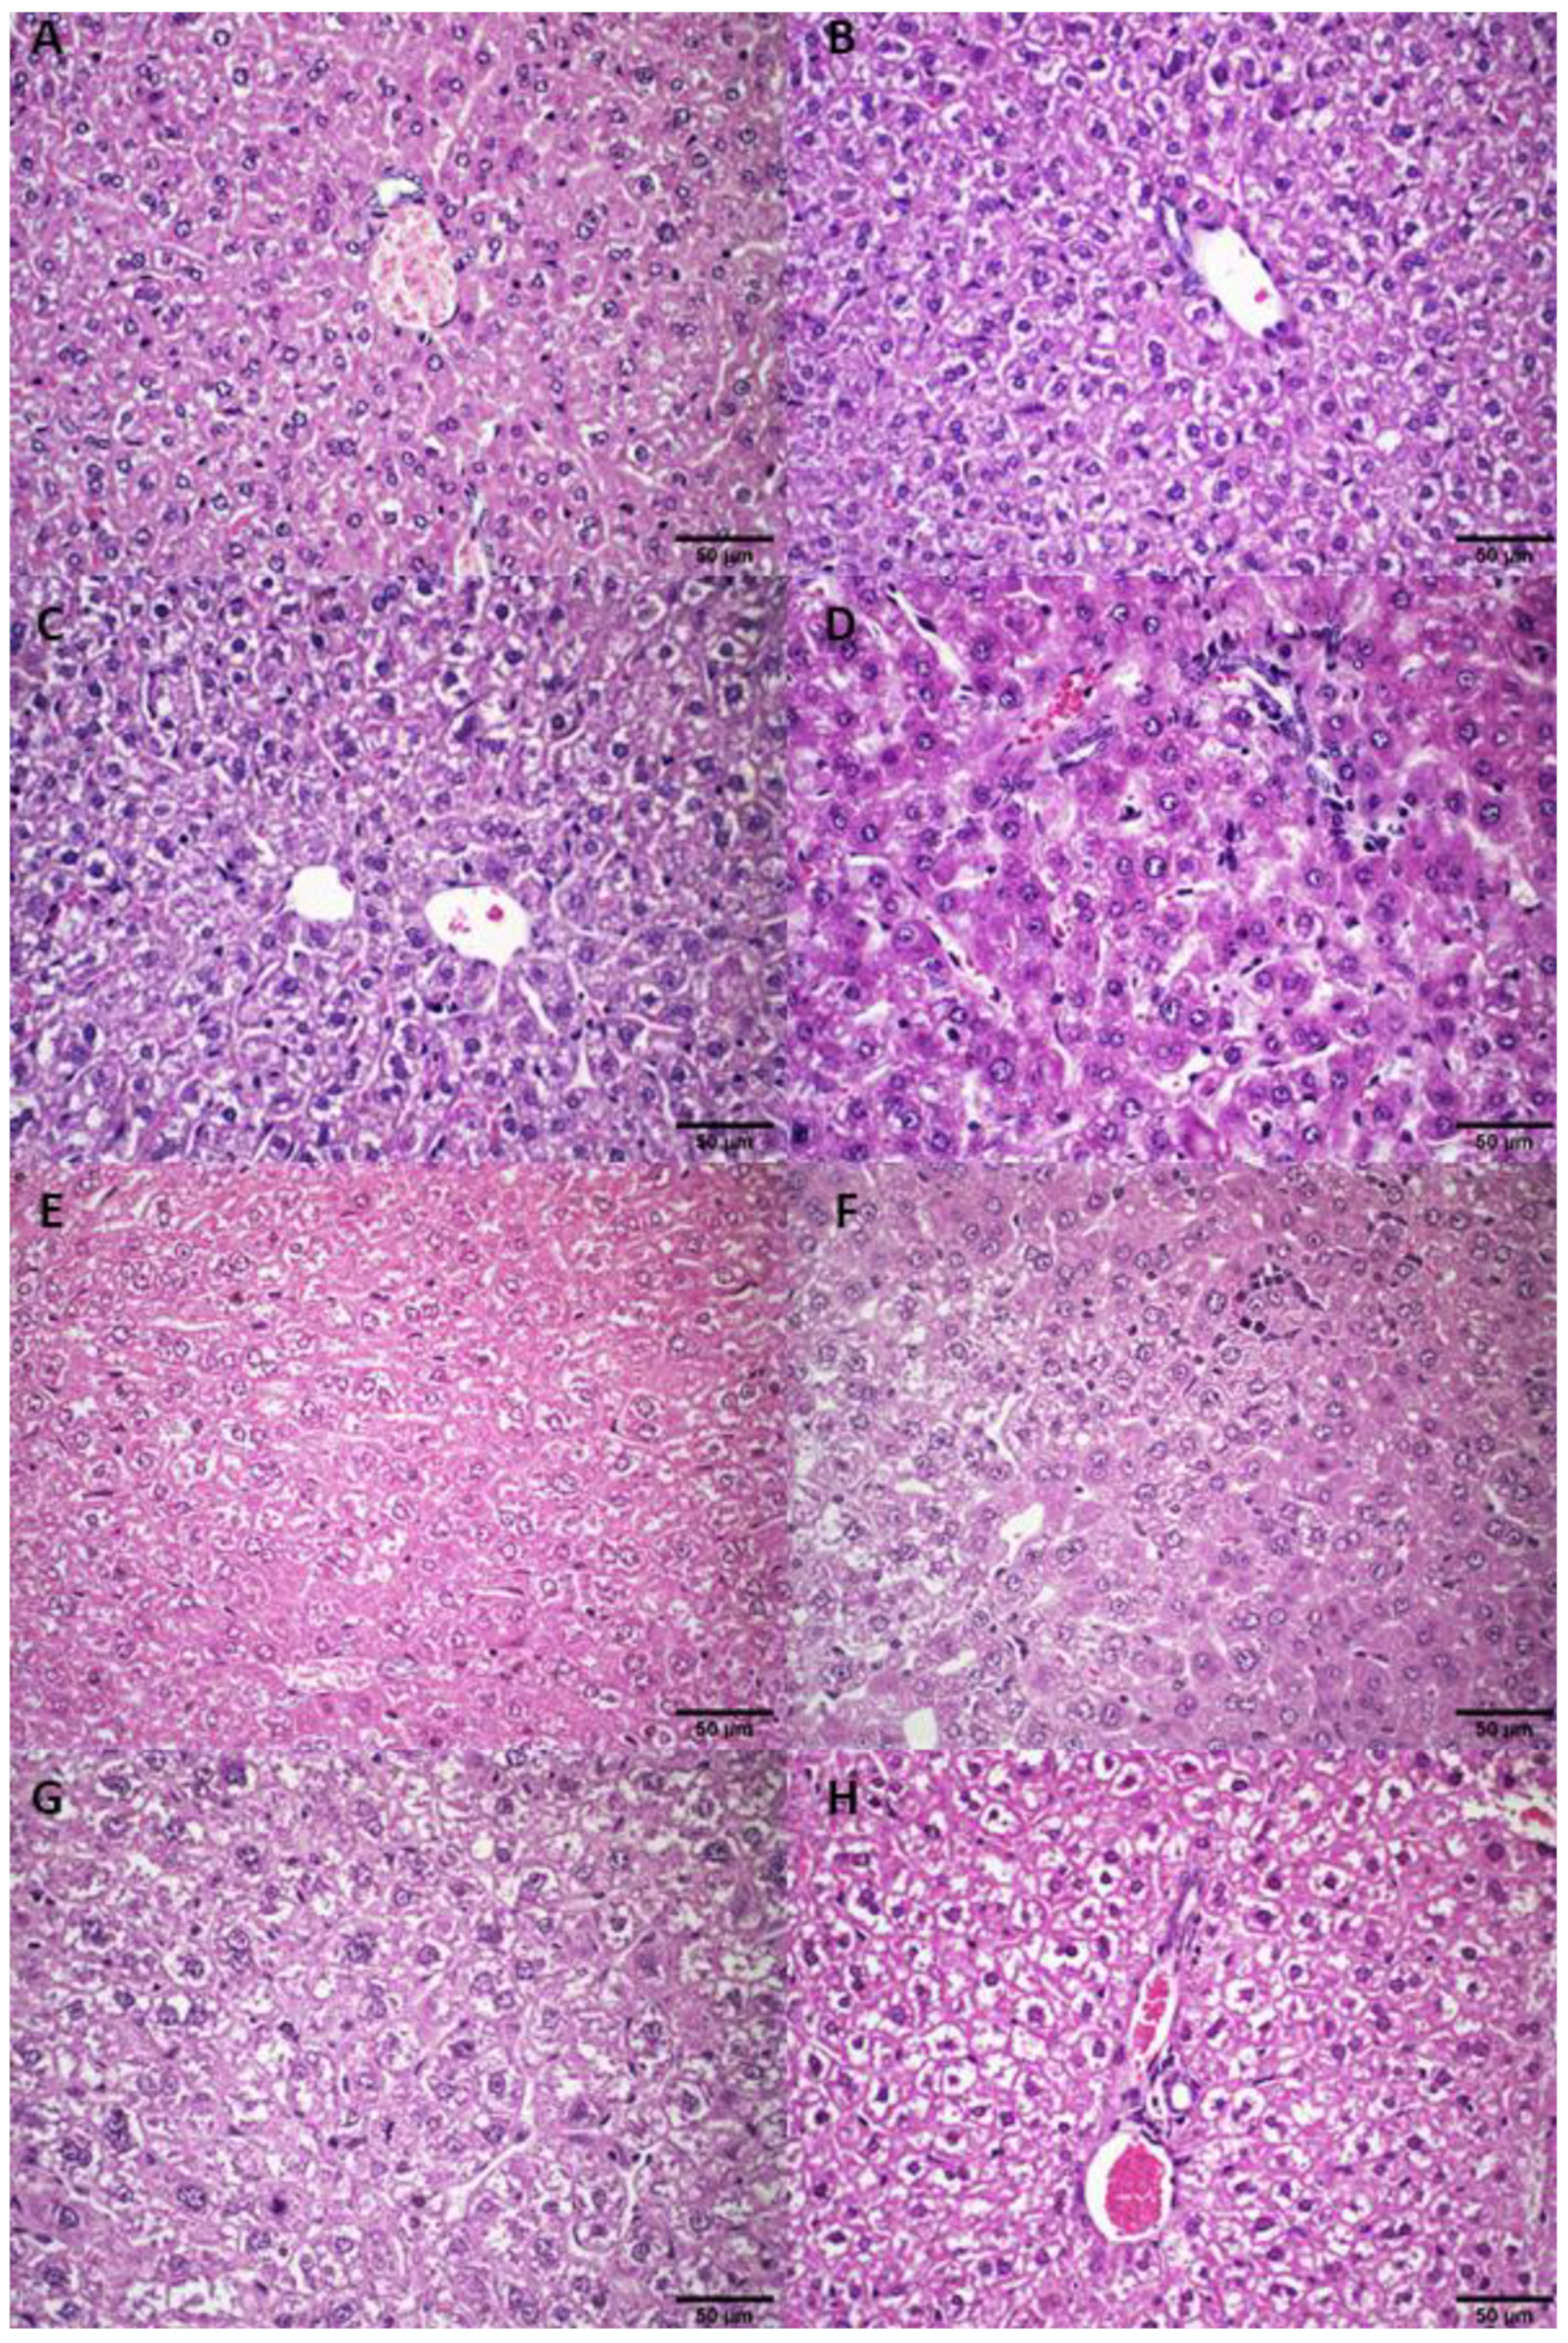

3.2.4. Histological Analysis

3.3.2. Histological Analysis